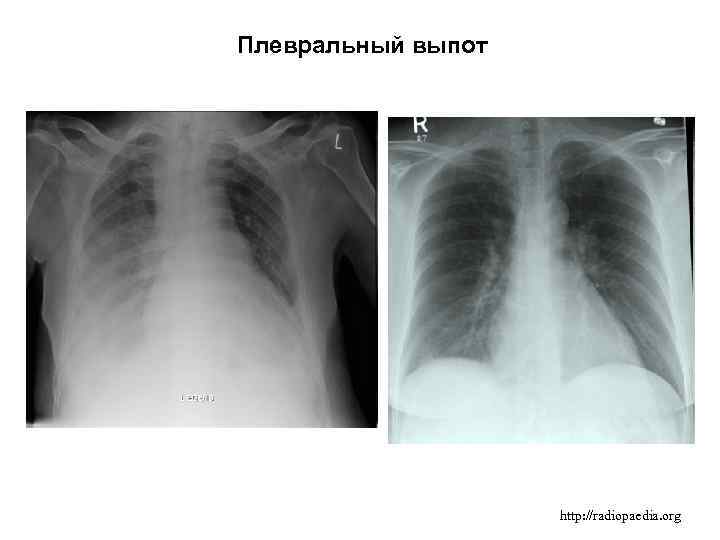

Диагностика плеврального выпота: что нужно знать